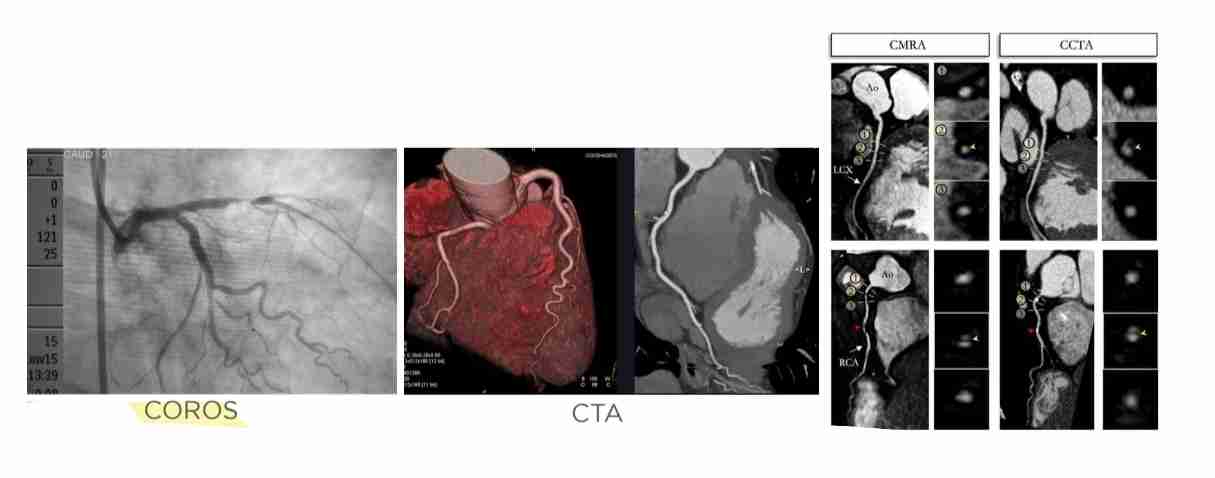

i. X-ray Coronary Angiography or “Angiogram”/ “COROS”

ii. Computed Tomography Coronary Angiography (CCTA)/“CT Angiogram”

iii. Coronary Magnetic Resonance Angiography (CMRA)